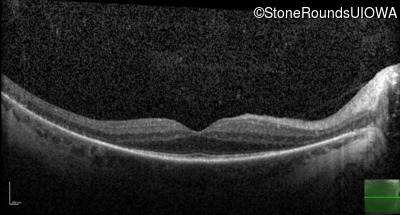

Age at visit: 33 years

OD OS